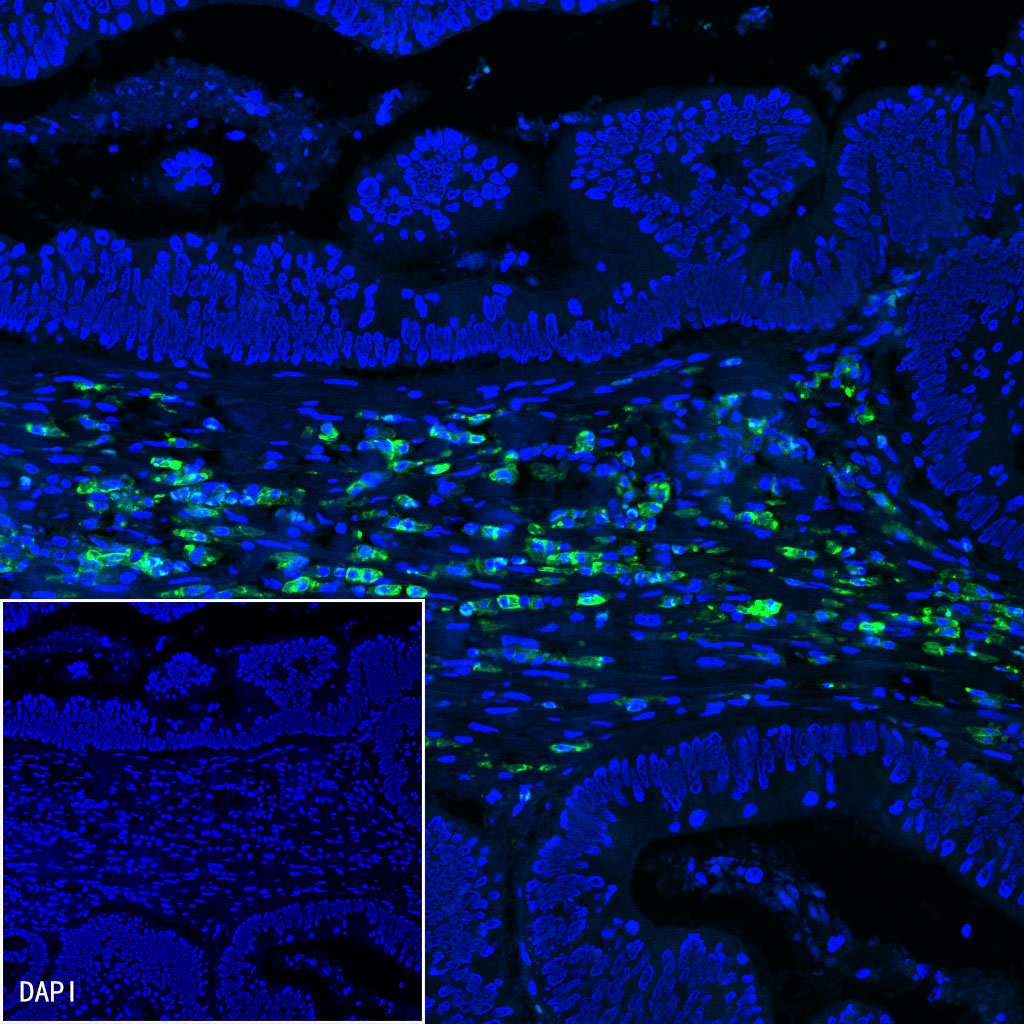

Immunofluorescence

IF shows positive staining in paraffin-embedded human cervical squamous cell carcinoma. Anti-CD38 antibody was used at 1/500 dilution (Green) and incubated overnight at 4°C. Goat polyclonal Antibody to Mouse IgG - H&L (Alexa Fluor® 488) (S0B4017) was used as secondary antibody at 1/500 dilution. Counterstained with DAPI (Blue). Heat mediated antigen retrieval with EDTA buffer pH9.0 was performed before commencing with IF staining protocol.